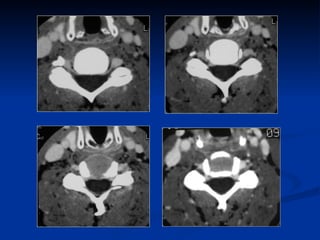

TDM cervicale  Acquisition hélicoïdale Matrice 512 x 512 Petite épaisseur de coupe Injection IV de PC: épidurographie Faible quantité de graisse dans le rachis cervical Reconstruction 2D/3D

TDM injectée Épidurographie Base de la sémiologie TDM des HD

TDM+INJECTION IV AVANTAGES Technique ambulatoire, généralisée Bonne visualisation des structures osseuses Bonne sensibilité Reconstruction 2D/3D LIMITES Artéfacts d’épaule Injection IV de PC jamais anodine Médiocre pour l’étude de la moelle Peu sensible en cas de dégénérescence débutante.

TDM injectée ÉpidurographieBase de la sémiologie TDM des HD

TDM+INJECTION IV AVANTAGESTechnique ambulatoire, généralisée Bonne visualisation des structures osseuses Bonne sensibilité Reconstruction 2D/3D LIMITES Artéfacts d’épaule Injection IV de PC jamais anodine Médiocre pour l’étude de la moelle Peu sensible en cas de dégénérescence débutante.